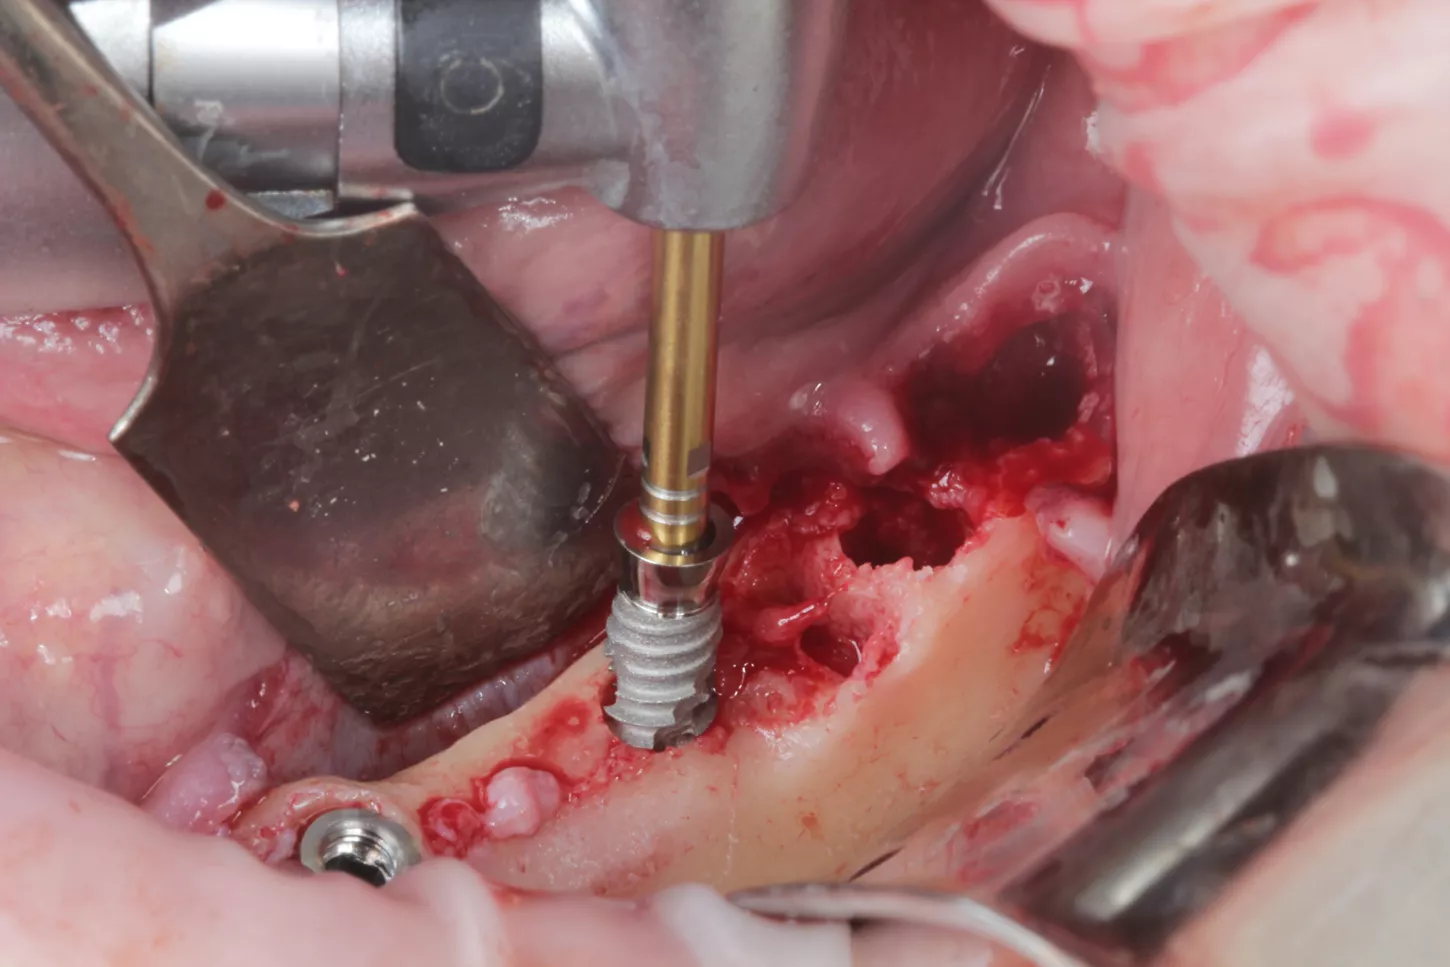

10. Drilling sequence conducted according to the Axiom X3® Tissue Level Ø 3.4 mm x 10mm, gingival height 2.5 mm implant, in this case being mandibular bone of D2, we stopped at the red drill of Ø 2.4/3.0 mm in the Axiom® Surgical Kit.

10

11a. 11b. Placement of the Axiom X3® Tissue Level implants.

11a

11b